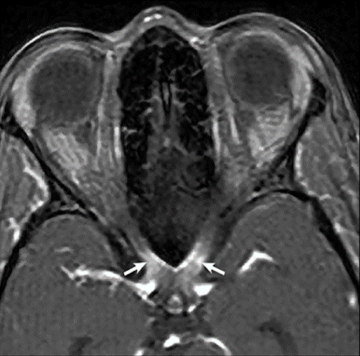

Проявления оптического неврита на МРТ при ЗСОНМ отличаются от таковых при РС: поражения продольно распространённые, односторонние и двусторонние с включением задних областей, а также распространяющиеся на хиазму и рядом расположенный гипоталамус.2,3

МРТ в режиме T1 с гадолинием (аксиальный срез) показывает накопление контрастного вещества в хиазме (белые стрелки)1